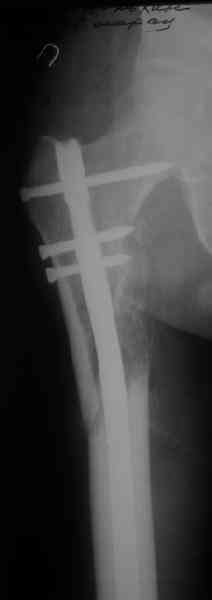

Re: ложный сустав !!!

СМ> Что, реально изогнуть титановый гвоздь, не сломав его?

Конечно. Чтобы не сломать, лучше проложить в тиски сразу ниже отверстий полоску металла, чтобы там создалась концентрация напряжений при изгибе, а не на уровне отверстия.

СМ> Если имеются под рукой Р-снимки, продемонстрируйте, плиз.

Вот несколько. С тисками и трубой на днях сделаем.